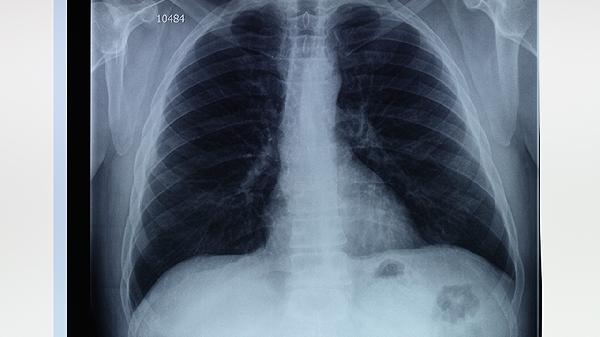

1、非小细胞肺癌

达伯舒适用于晚期或转移性非小细胞肺癌的治疗,尤其是EGFR基因突变阴性和ALK基因突变阴性的患者。临床研究表明,与化疗相比,达伯舒可显著延长患者的无进展生存期和总生存期。治疗中需定期监测免疫功能,并注意可能出现的皮疹、疲劳等副作用。